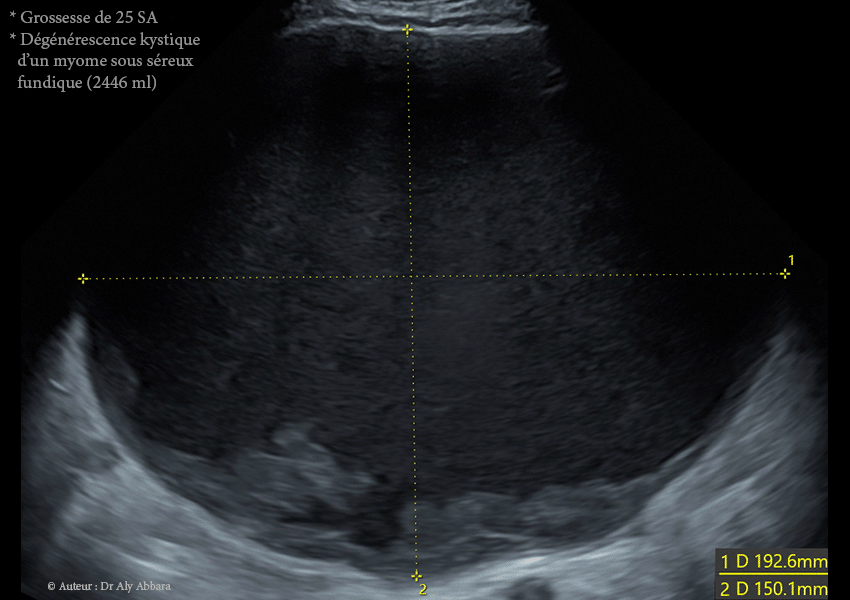

• Il s'agit d'un volumineux myome de 162.7 x 192.6 x 150.1 mm de diamètre, soit = 2446 cm3, découvert fortuitement lors de la première échographie de datation (à 10 SA puis à 12 SA), chez une jeune femme, primipare de 31 ans.

• On remarque échographiquement que ce myome qui présentait à 17 SA, dans sa partie centrale, de nombreuses zones liquidiennes enkystées de nécrobiose aseptique,

à 25 SA ce phénomène de (dégénérescence kystique du myome utérin) est devenu total : le myome a bien augmenté de volume (2446 ml contre 952 cm3 à 12 SA, soit une multiplication de volume par 2,6) ; il apparaît comme une énorme formation kystique à contenu trouble, hypoéchogène avec des plages d'aspect nuageux de résidus flottant (nécrotiques).

• À 25 SA : dégénérescence kystique quasi totale ; volume maximal de (2446 ml).